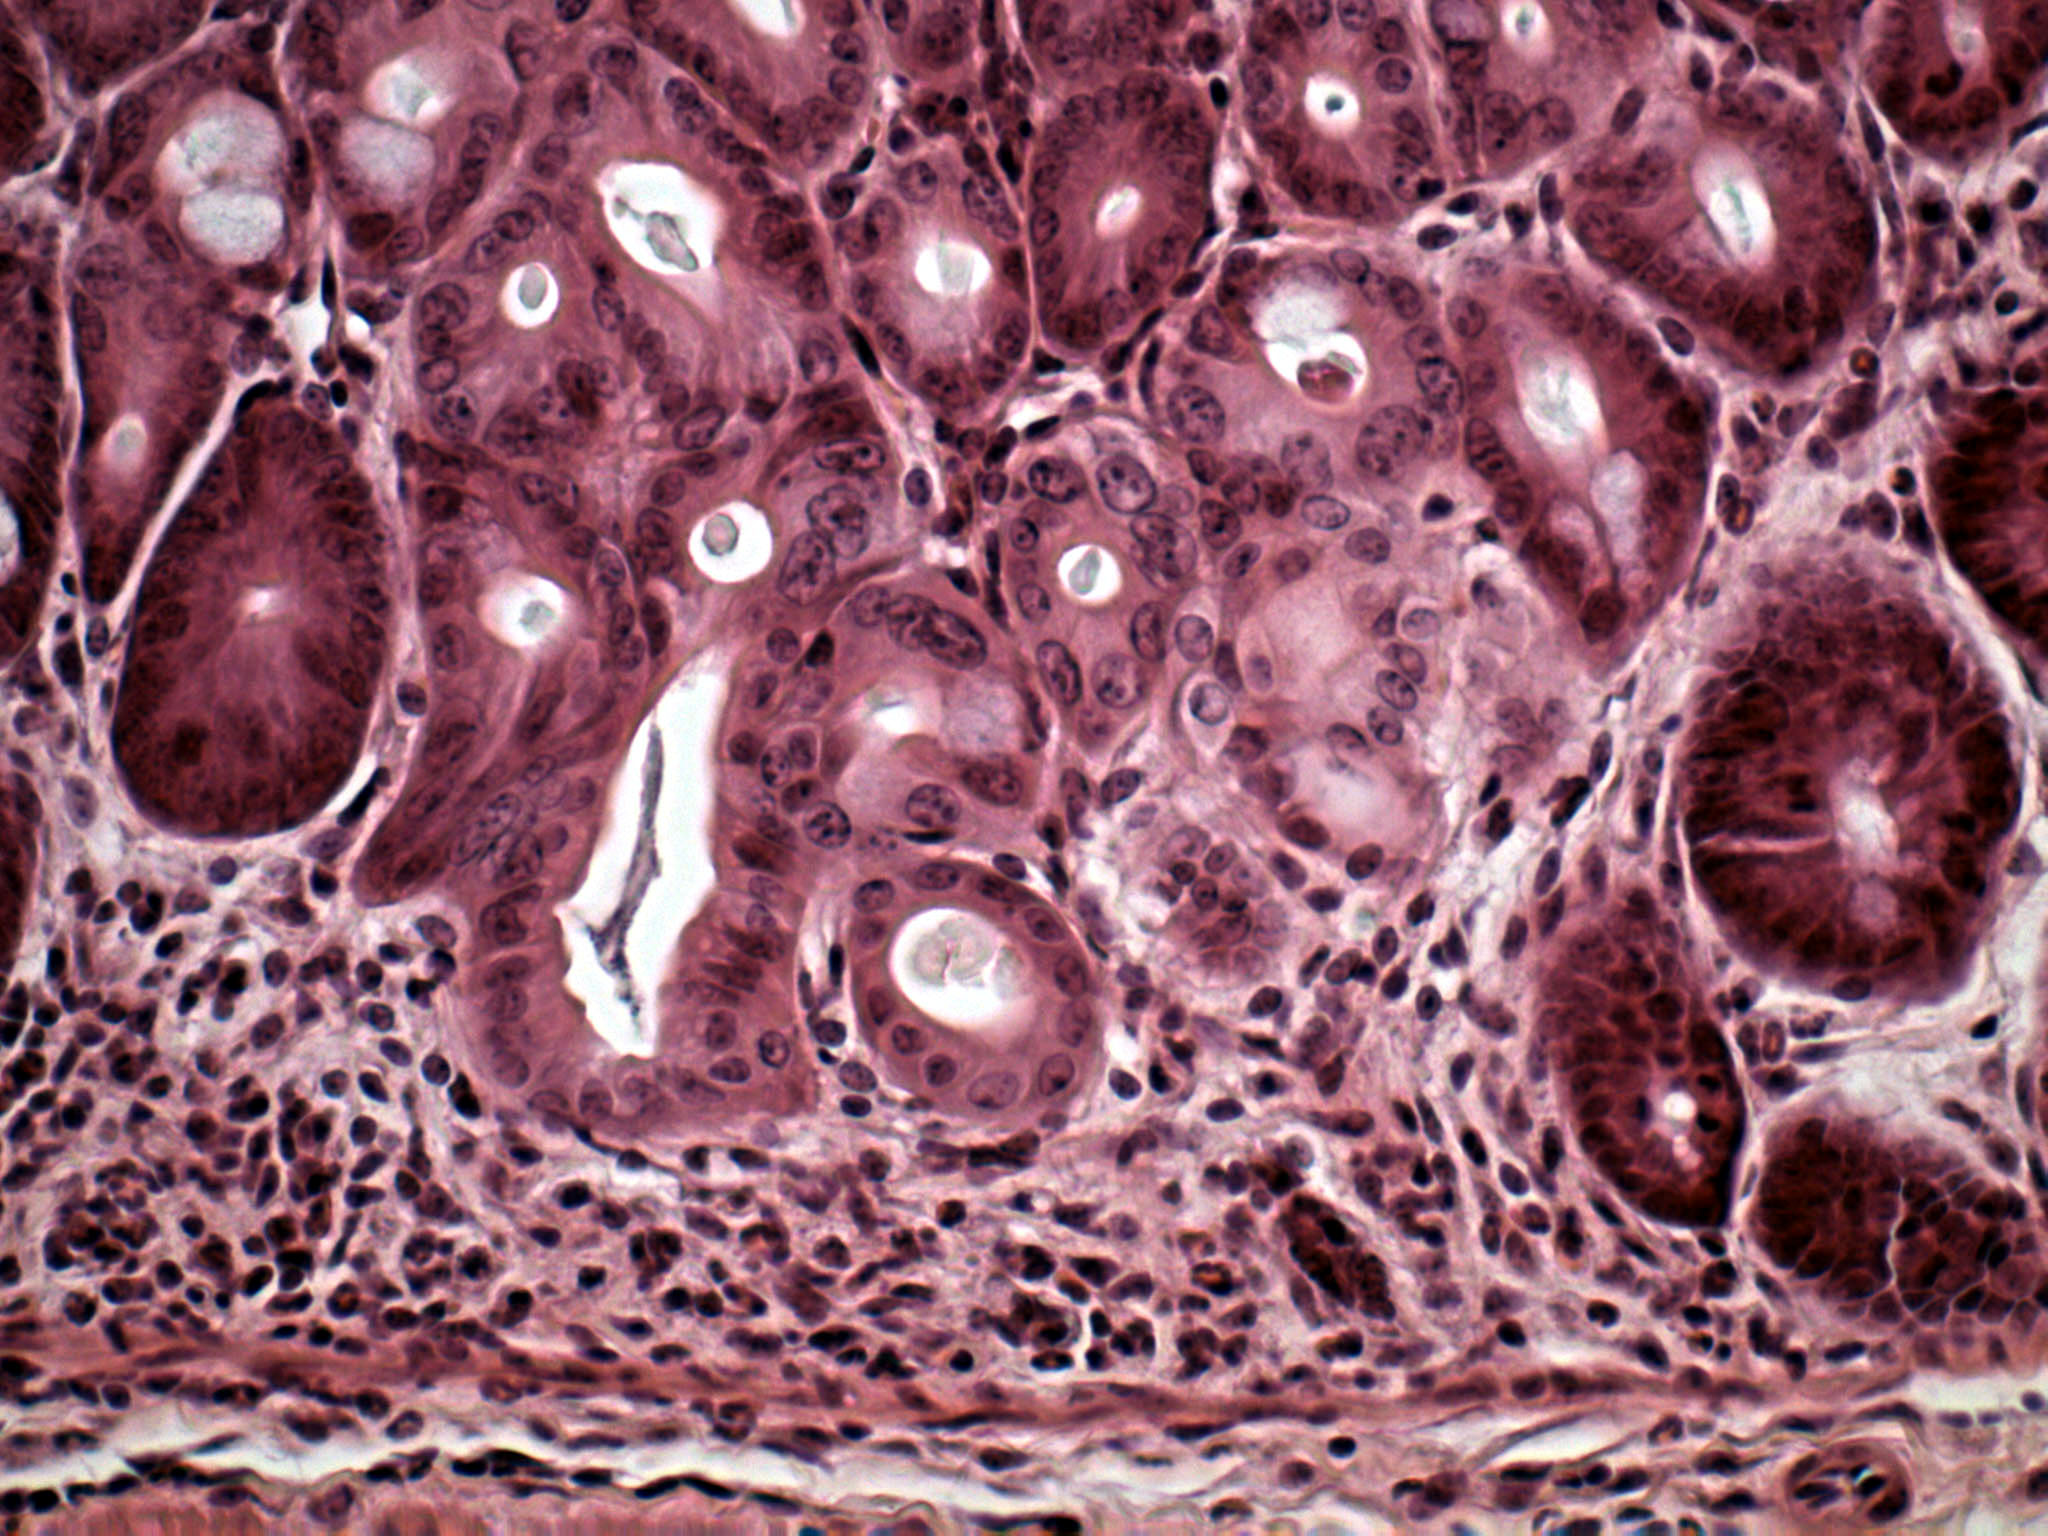

Mäuse mit einer Neigung zur chronischen Darmentzündung sollen der medizinischen Forschung helfen, neue Heilverfahren zu entwickeln. Bei der Untersuchung dieser Tiere stießen Forscher der Gesellschaft für Biotechnologische Forschung (GBF) in Braunschweig auf eine mögliche Erklärung für das bislang noch wenig verstandene Krankheitsbild. Die Ursache von chronischen Darmentzündungen wie etwa Morbus Crohn ist - so legen ihre Ergebnisse nahe - eine Autoimmunerkrankung, also eine Fehlsteuerung von Abwehrzellen des Immunsystems. Ihre Erkenntnisse beschreiben die Forscher in der jüngsten Ausgabe der Zeitschrift Gut, eines Fachmagazins für Darmerkrankungen.

Das haben Buer und seine Arbeitsgruppe jetzt getan. Sie kreuzten eine Zuchtlinie von Mäusen, deren Darm-Zellen ein besonderes Proteinmolekül auf ihrer Oberfläche tragen - ein so genanntes Antigen - mit einem Mäuse-Stamm, der gegen genau dieses Antigen aggressive Immunzellen produziert. Das Ergebnis sind Mäuse, deren Abwehrsystem die eigene Darmschleimhaut angreift. Darmentzündung ist die Folge.

"Dieser Zustand ähnelt stark dem von menschlichen Patienten, die unter einer der vielen chronischen Formen der Darmentzündung leiden", erläutert Dr. Astrid Westendorf, eine Forscherin in Buers Arbeitsgruppe. Zu diesen Erscheinungsbildern der Krankheit gehören Morbus Crohn und Colitis ulcerosa. Sie äußern sich in regelmäßig wiederkehrenden schmerzhaften Darmkrämpfen, Durchfall und Darmblutungen. Allein an Morbus Crohn leiden in Deutschland nach Schätzungen 100 000 Menschen, in den USA sind es mehr als 400 000. Professor Buer: "An unseren Mäusen können wir jetzt viele Eigenschaften solcher Krankheiten studieren. Wann entstehen sie? Wie verlaufen sie? Wann gibt es akute Ausbrüche? Und vor allem: Wie kann man sie heilen?"